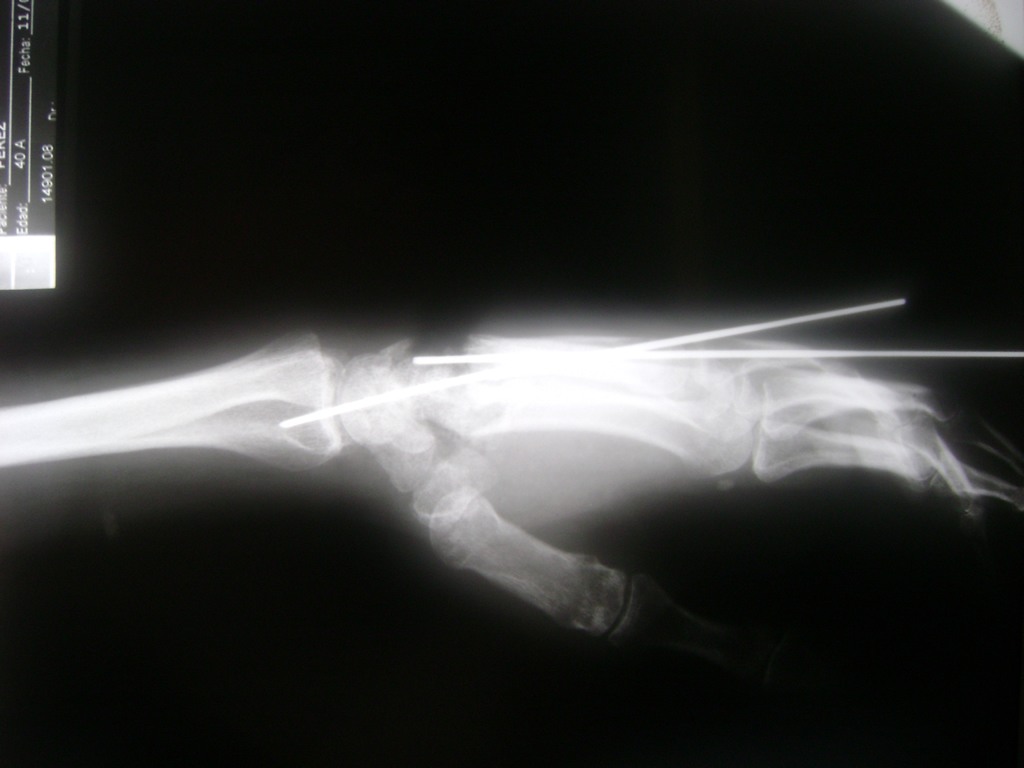

Cirugías de Húmero - Cirugías de Muñecas y Manos

Los procedimientos más comunes en cirugía de la mano son aquellos destinados a reparar traumatismos, incluyendo lesiones de tendones, nervios, vasos sanguíneos, y articulaciones; huesos fracturados; y quemaduras, cortes, y otros daños de la piel.